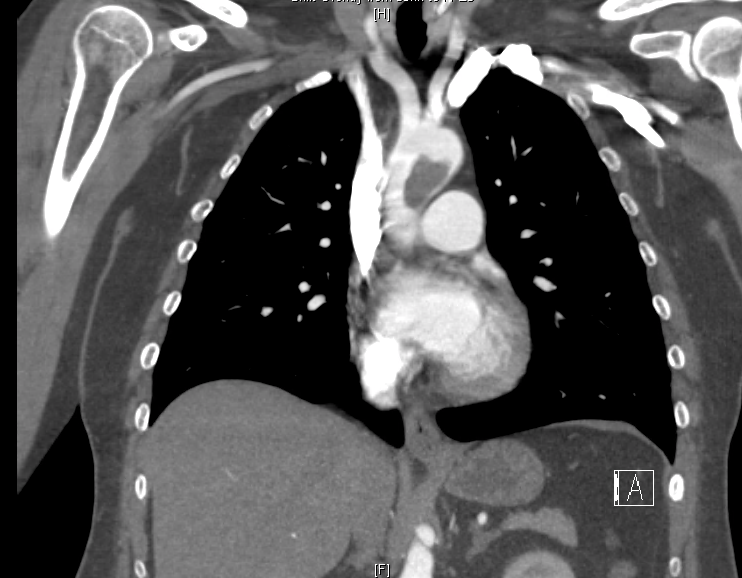

Ct Angiography Showing A Thrombus In The Pulmonary Artery Branches Download Scientific Diagram